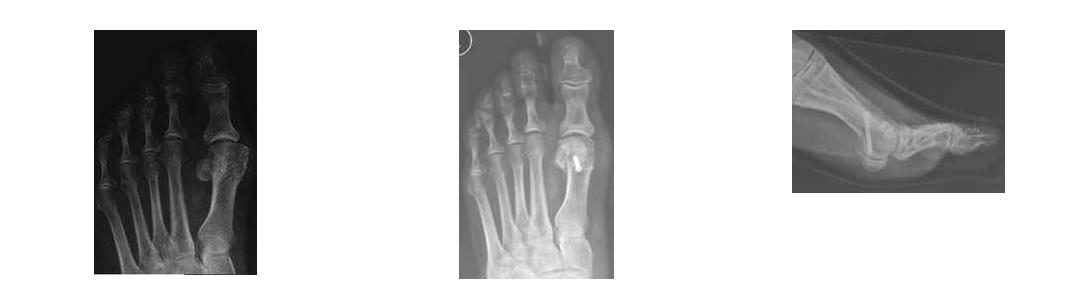

Hallux valgus

Die häufigste Vorfußdeformität ist in der Regel durch einen Spreizfuß verursacht. Mit zunehmender Ausprägung der Deformität kommt es zum Schuhkonflikt und zu einer Kompromittierung der benachbarten Zehen, die von der Großzehe verdrängt wird.

Abhängig von den gemessenen Winkeln im Röntgenbild wird das operative Verfahren gewählt. Je ausgeprägter die Fehlstellung, desto aufwändiger ist das operative Verfahren. Im Folgenden werden verschiedene operative Verfahren anhand von Beispielen vorgestellt, die an unserer Klinik durchgeführt werden.

Arthrose des Großzehengrundgelenks

Bei der Arthrose des Großzehengrundgelenks kommt es zur zunehmenden schmerzhaften Bewegungseinschränkung des Gelenks. Im Röntgenbild kann dies erkannt werden. An Behandlungsmöglichkeiten stehen zu Beginn Spezialeinlagen und/oder Abrollhilfen am Schuh zur Verfügung. An operativen Therapiemöglichkeiten kommen zu Beginn noch gelenkerhaltende Operationen, bei weit fortgeschrittener Arthrose kommt die Versteifung dieses Gelenkes in Frage.